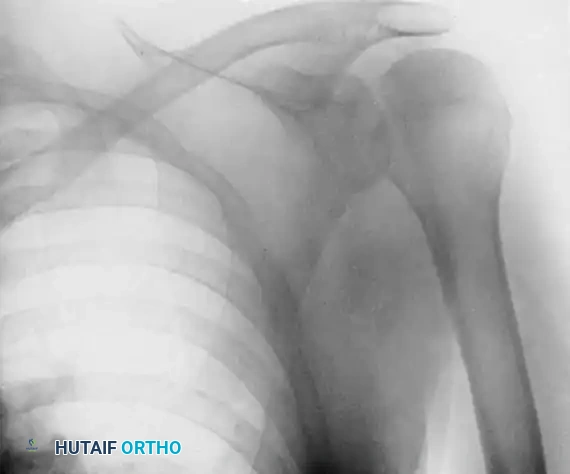

Clinical Pearl: Posterior dislocations are notoriously missed on initial presentation. As demonstrated in the radiographs above, an anteroposterior (AP) radiograph may show only subtle changes, such as the "lightbulb sign" or loss of the normal elliptical overlap of the humeral head and glenoid. An axillary lateral radiograph is absolutely mandatory to confirm the posterior displacement of the humeral head and to quantify the extent of the anterior impression defect where the posterior glenoid rim is incarcerated.